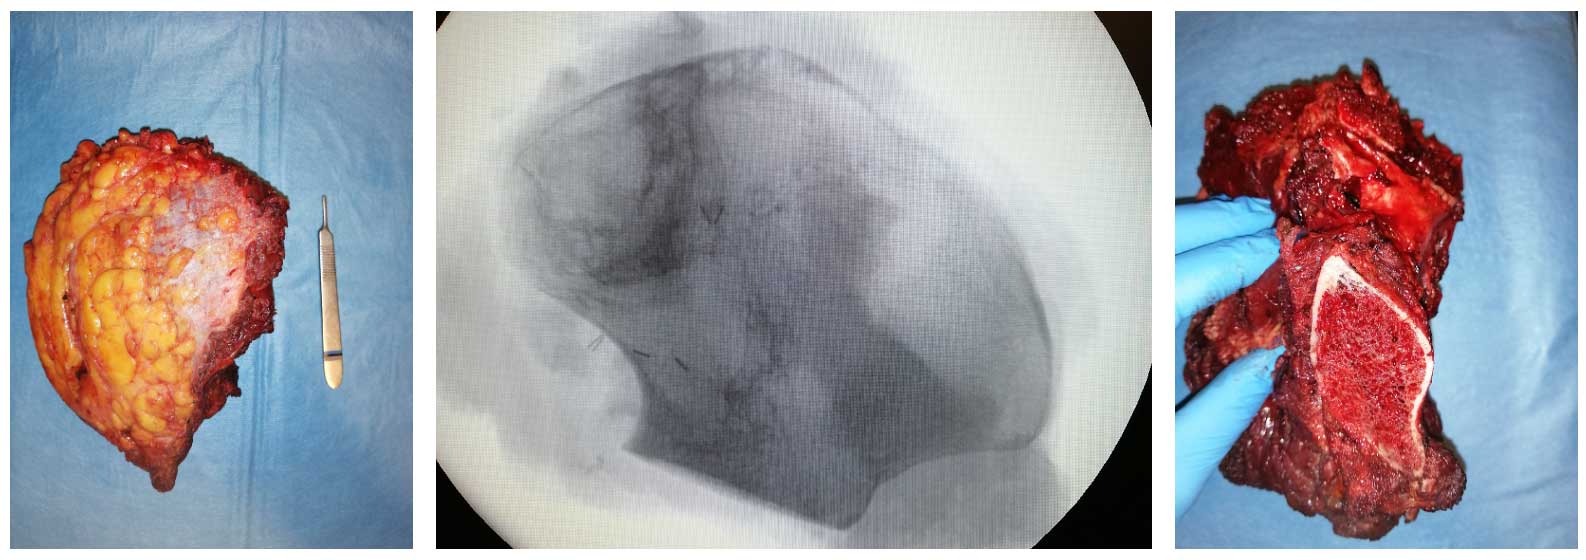

Ameliyat Esnası: Çıkarılan tümörün klinik ve radyolojik görüntüsü.